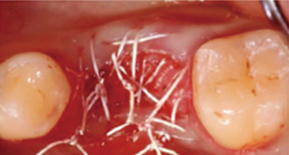

1. Exposing bone after incision

2. Large implant hole after multiple drilling

3. Placing implant

4. Suture